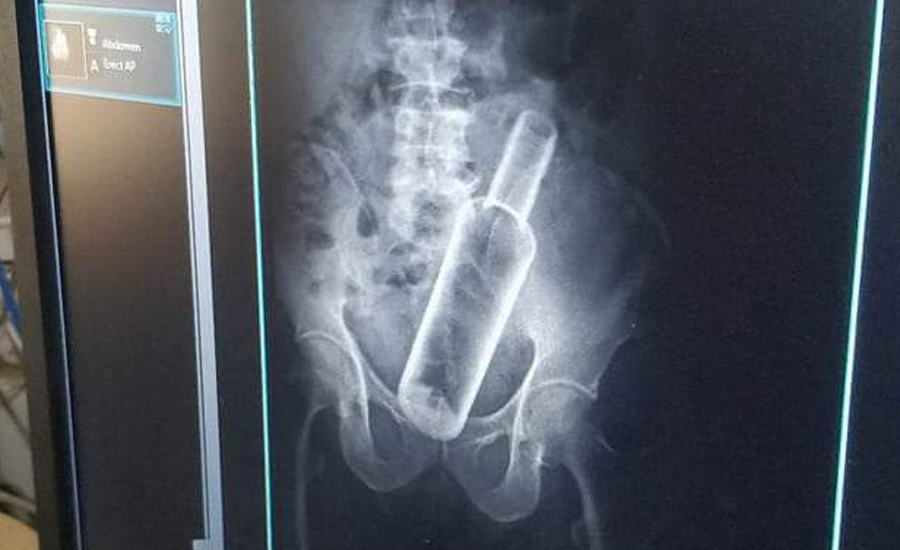

६१ वर्षीय जमनसिंहको पेटमा भेटियो रक्सीको बोत्तल

काठमाडौं । धनगढीको सेती प्रादेशिक अस्पतालमा उपचार गर्न आएका एक बिरामीको पेटमा रक्सीको बोत्तल भेटिएको…